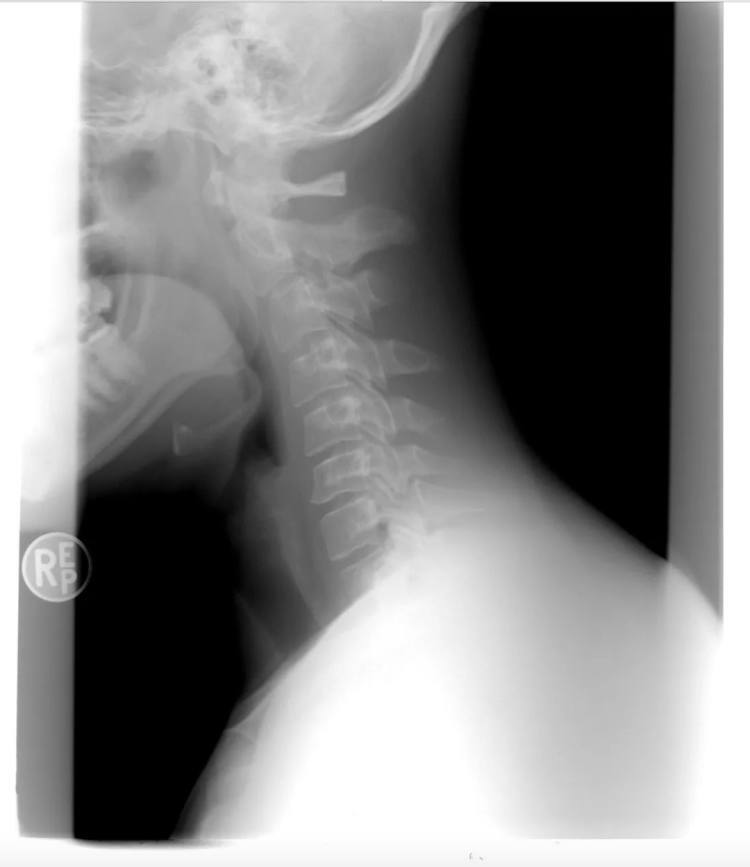

丁俊明是某大厂的软件开发程序员,颈椎病也伴随了他5年之久。27岁那年,丁俊明去医院看颈椎病。经过各项检查后,医生非常严肃地告诉他:“你这颈椎真不像是27岁的啊,像60岁的。”

图片

颈椎X光片。(图/pixabay)

检查结果显示,丁俊明的颈椎变形程度已经非常明显,多节椎间盘突出,纤维环已经破裂。医生说如果不及时进行干预,后果不堪设想。这些年,丁俊明忙于工作,实在受不了了才会到医院理疗。他尝试过各种治疗方式,除了颈椎牵引,还做过电针疗法,吃过中药。